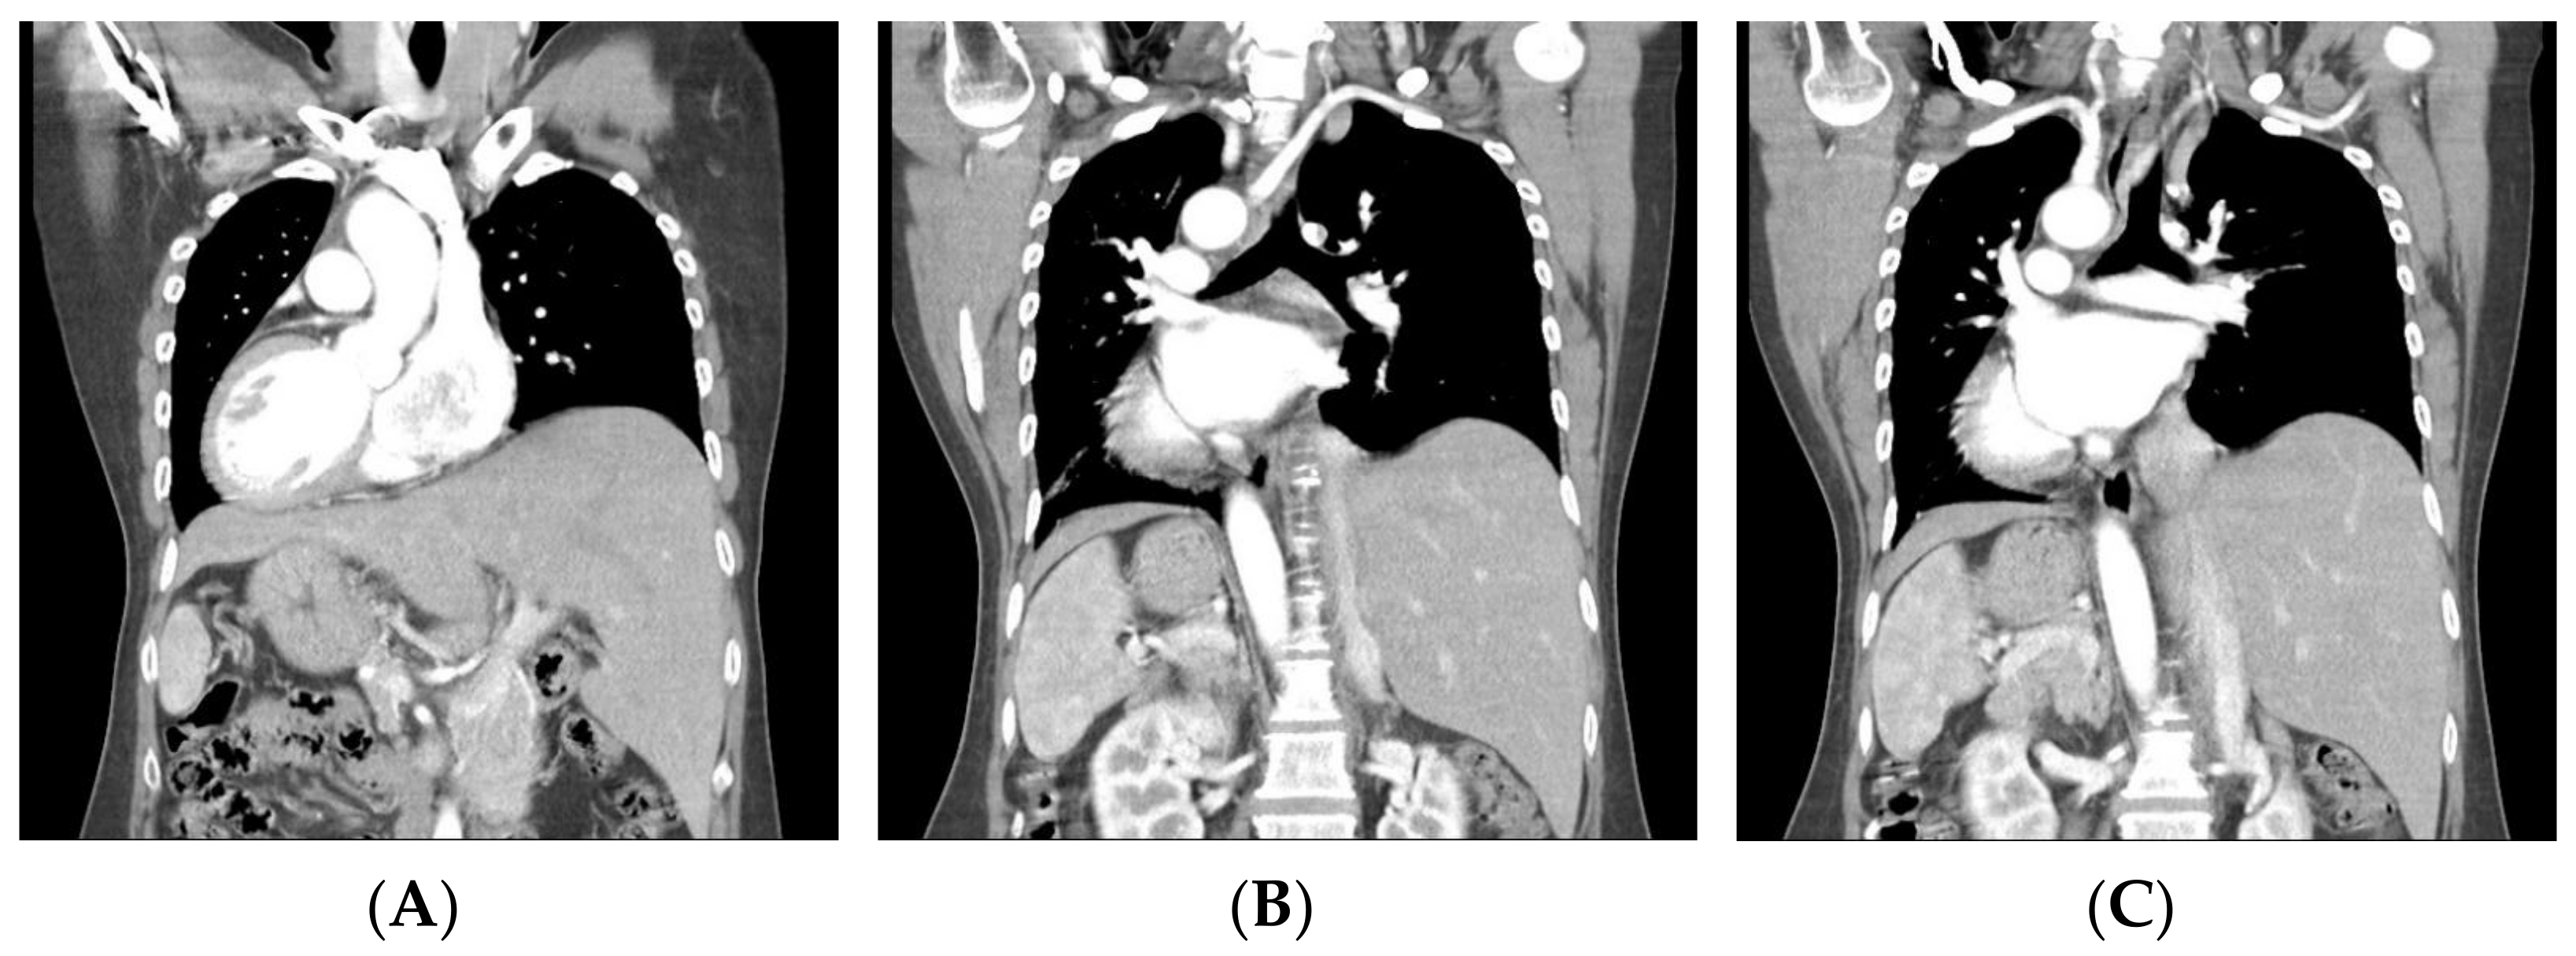

Figure 1. Preoperative computerized tomography (CT) revealing inversus totalis (A) with arterial malformation of left aberrant subclavian artery (B,C). This case concerns a 48-year-old woman who presented with a palpable left neck mass and occasional dysphagia. She had a history of thyrotoxicosis under medication control, and the last thyroid function test showed euthyroid status. She denied other systemic diseases. Physical examination showed a firm palpable nodule (about 2 cm in diameter) over the left thyroid lobe. Preoperative chest X-ray showed dextrocardia. The ultrasound scan of the neck revealed a left thyroid nodular goiter sized 2.1 × 1.7 cm2 with microcalcification. Fine-needle aspiration cytology was negative for malignant cells. The patient’s head and neck CT revealed not only dextrocardia with right aortic arch and aberrant left subclavian artery, but also left-sided liver and right-sided spleen, suggesting inversus totalis (Figure 1). The patient had a left lobectomy with isthmusectomy. Intraoperatively, a left-sided NRLN was dissected and preserved (Figure 2). Surgical histopathology report confirmed nodular goiter with islands of colloid-filled acini and islands of small hyperplastic acini. There was no sign of hoarseness during the postoperative period and the patient was discharged under stable condition without relative complication. In general, RLN runs into the tracheoesophageal groove, with other routes including the paratracheal area or the paraesophageal area [1]. For head and neck surgery, visualization and preservation of RLN are vital steps to prevent or minimize nerve injury. The NRLN, a rare variant of RLN, imposes a higher surgical risk of nerve injury. In the much rarer case of left NRLN, such as the case of our patient, the whole vascular and nerve development process is enantiomorphic, resulting in the inversus totalis, accompanied by left aberrant subclavian artery and left NRLN [2]. Preoperative identification of aberrant subclavian arteries and NRLNs is essential for reducing the potential risk of nerve damage. Several imaging modalities have shown their potential of preoperative detection of relevant variants. The ultrasonography pattern of the right common carotid artery at its origin level is normally seen as the “Y-sign”, since the right common carotid artery arises from the bifurcation of the brachiocephalic trunk. On the other hand, if the perioperative ultrasonography showed a right common carotid artery arising directly from the aortic arch, the right aberrant right subclavian artery and the associated right NRLN should be suspected [3]. Moreover, preoperative Computed Tomography and CT angiography are safe and convenient tools that can provide more precise images of vascular structure and promote early detection of relative anomalies of aberrant arteries and NRLN.

Diagnostics 12 00730 g001